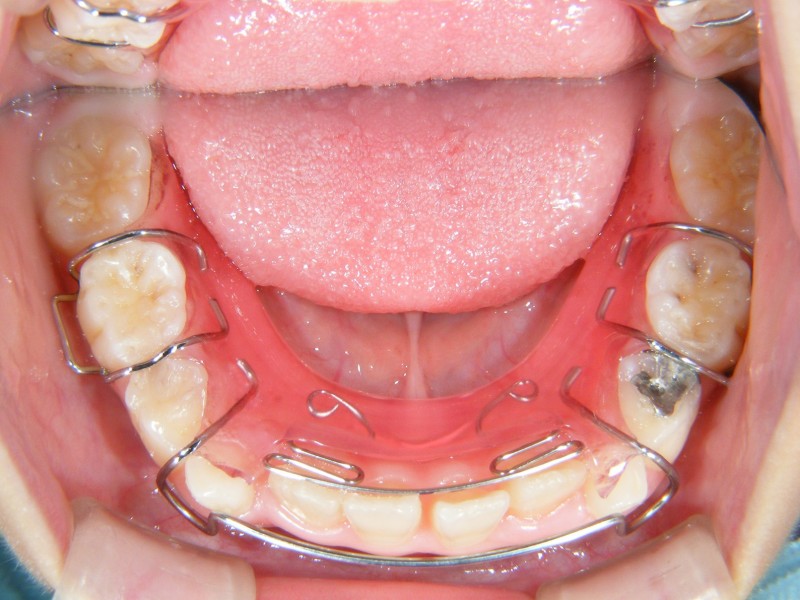

拡大床と言われる、着脱式の矯正装置をセットしました。

1日、14時間以上装着していただきます。

音楽の時間や、体育の時間、給食の時間等、必要な時は外します。

ご自宅で、装置のネジを3日に1度回して、装置を少しずつ広げていきます。

少し広がった装置をお口にセットすることで、歯列が少しずつ広がっていきます。